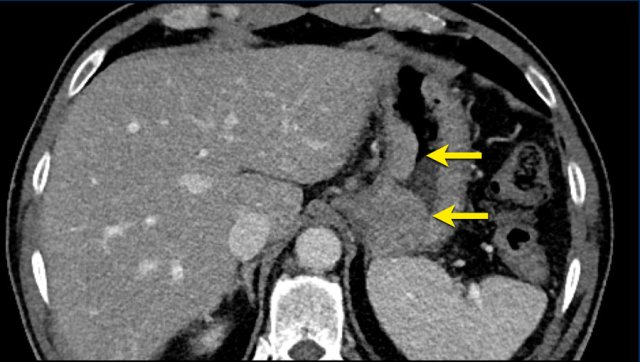

CT images in a 73-year-old male with progressive liver metastases of colorectal carcinoma.

This is anothe example of progression of non-target lesions.

Even if there is partial response or even disappearance of other lesions, this is still progressive disease.